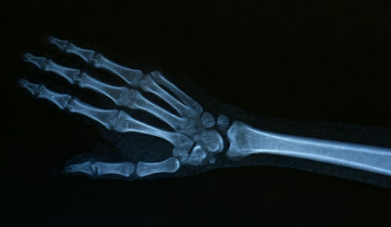

Q4. CRPS는 MRI나 CT로 진단되나요?

A. 영상 검사로 직접 진단하긴 어렵고, 임상 증상과 이학적 검사로 판단합니다. 뼈 스캔, 감각 검사 등이 보조적으로 사용됩니다.